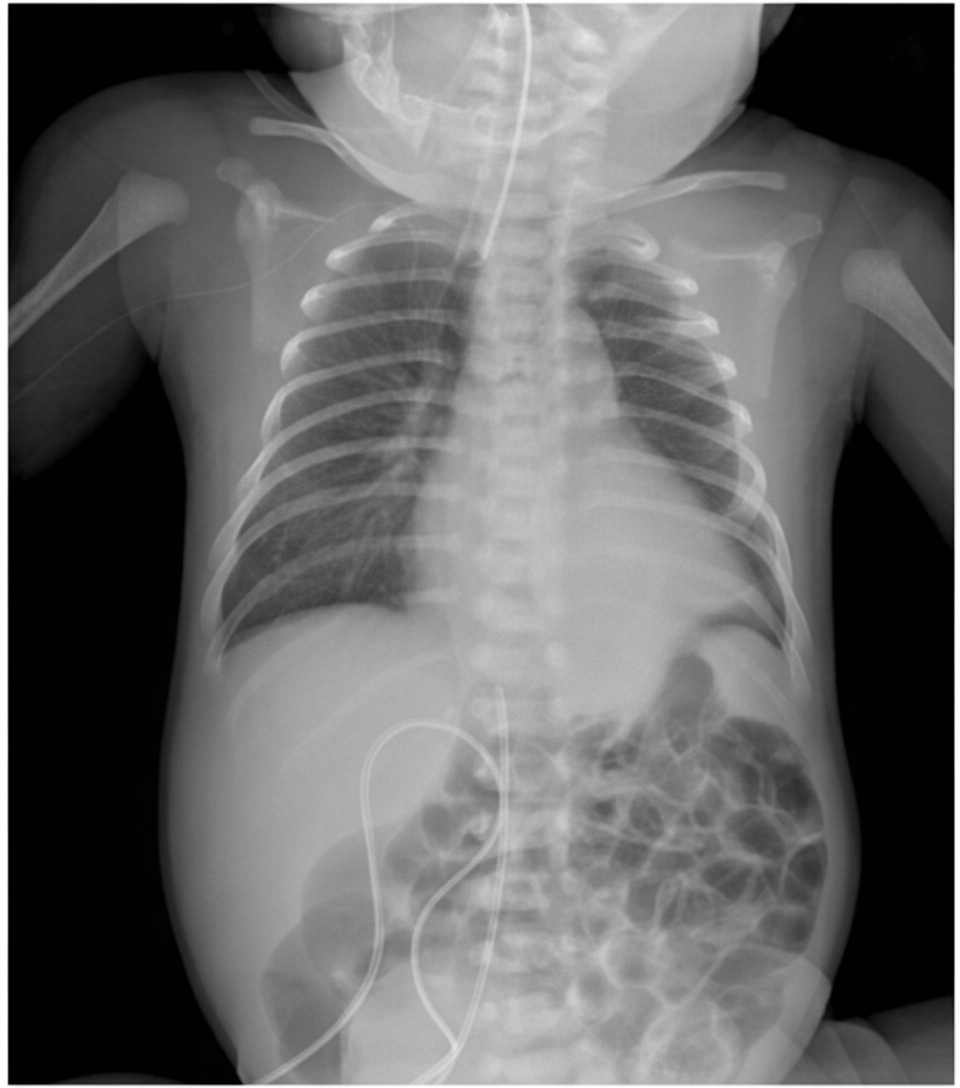

An infant presents with respiratory distress. What is the diagnosis based on the provided X-ray?

Explanation: ***Diaphragmatic hernia*** - Classic X-ray findings include **bowel loops** visible in the thoracic cavity with **mediastinal shift** away from the affected side. - Presents with **severe respiratory distress** in newborns due to lung compression and **pulmonary hypoplasia**. *Bronchiectasis* - Typically seen in **older children** with chronic respiratory infections, not in newborns. - X-ray shows **thickened bronchial walls** and **honeycomb appearance**, not bowel loops in chest. *Hyaline membrane disease* - Shows characteristic **ground-glass opacity** with **air bronchograms** throughout both lung fields. - Associated with **surfactant deficiency** in premature infants, not bowel displacement into thorax. *Pneumatocele* - Appears as **thin-walled air-filled cysts** within lung parenchyma, typically following pneumonia. - Usually develops **post-infection** in older infants, not as a congenital condition in newborns.